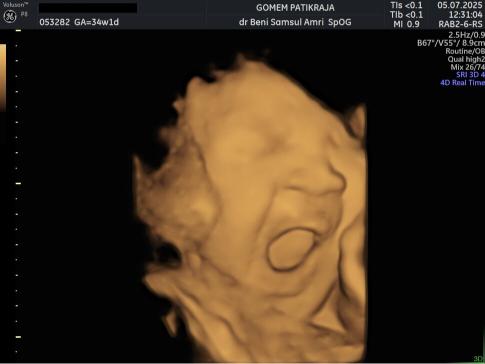

USG Janin 34 Minggu

Informasi Minggu Ke-34

Perkembangan Janin 34 Minggu:

Sistem pencernaan janin sudah siap untuk mengolah ASI pertama atau kolostrum. Meski ruang geraknya terbatas, ia tetap aktif melakukan peregangan. Organ penglihatannya sudah bisa menangkap bayangan cahaya yang masuk.